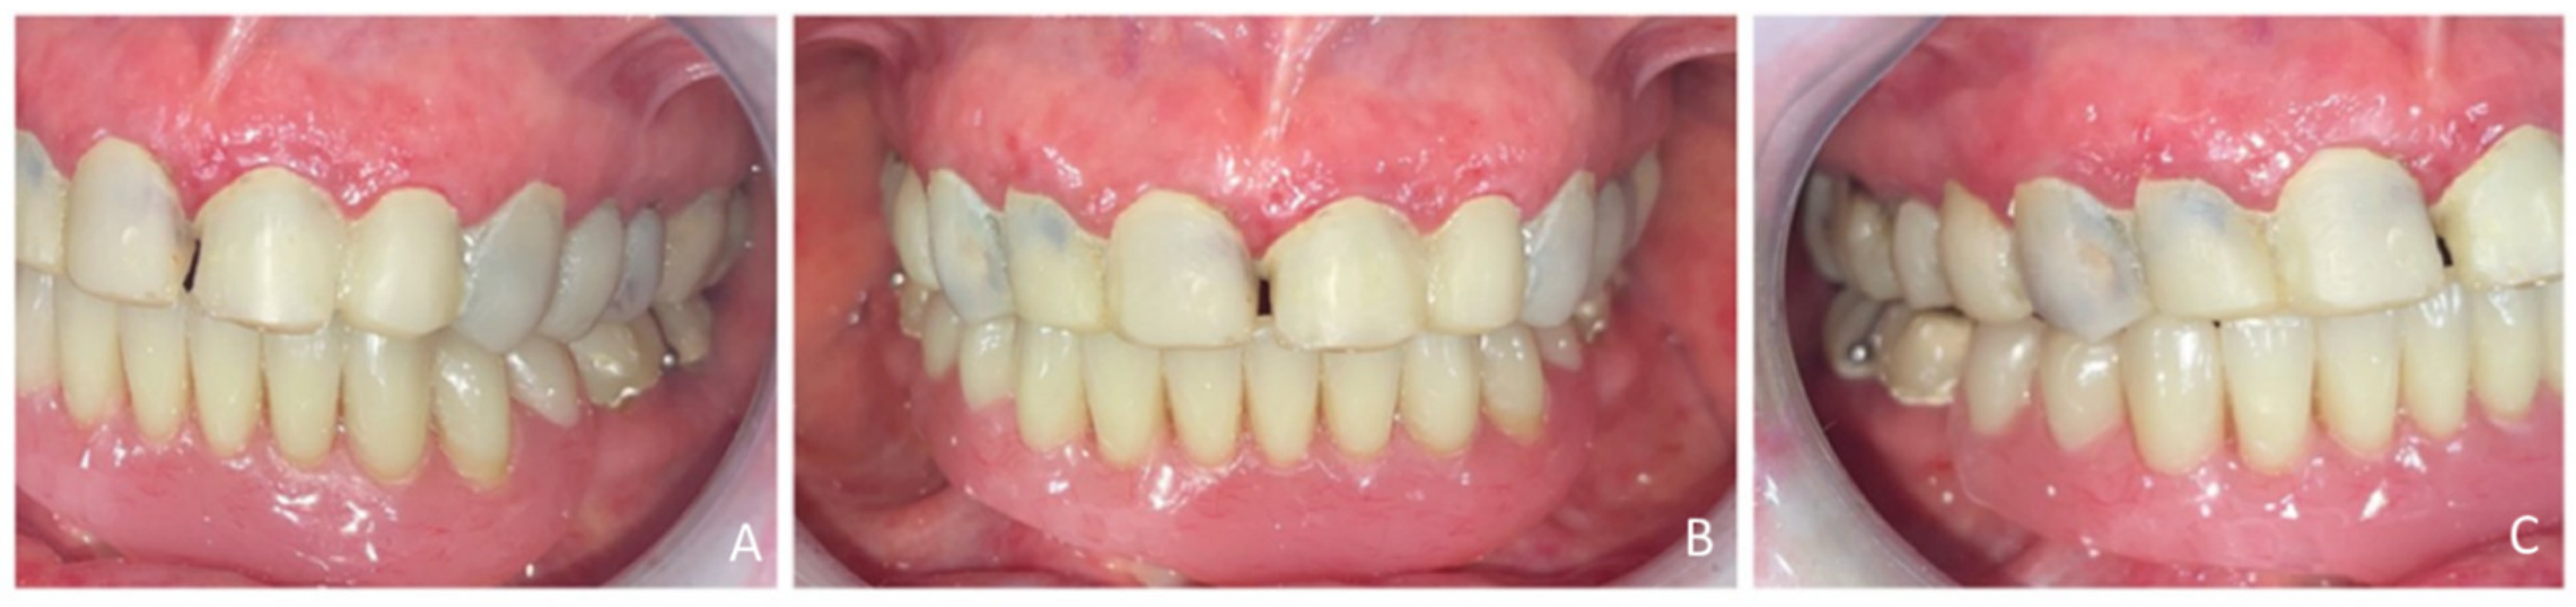

Extraoral examination revealed an unaesthetic smile, radiation-induced caries (Figure 1A), and mandibular retrognathia following carcinoma resection. The occlusal vertical dimension (OVD) was slightly reduced. Intraoral examination showed extensive decay in the remaining teeth (17 to 27, 36, 37, 46, and 47), with most being painful to percussion and highly sensitive to cold. Compromised restorations were noted in teeth 17, 16, 14, and 26 (Figure 2). The gingiva was inflamed and extremely sensitive, and the alveolar ridge in the mandibular incisal region was severely resorbed. Radiographic examination confirmed that 26 and 17 were non-restorable due to advanced root decay and periodontal disease (Figure 3).

Figure 2.

Endo buccal examination: (A) maxillary arch, (B) mandibular arch, (C) dental arches in occlusion.